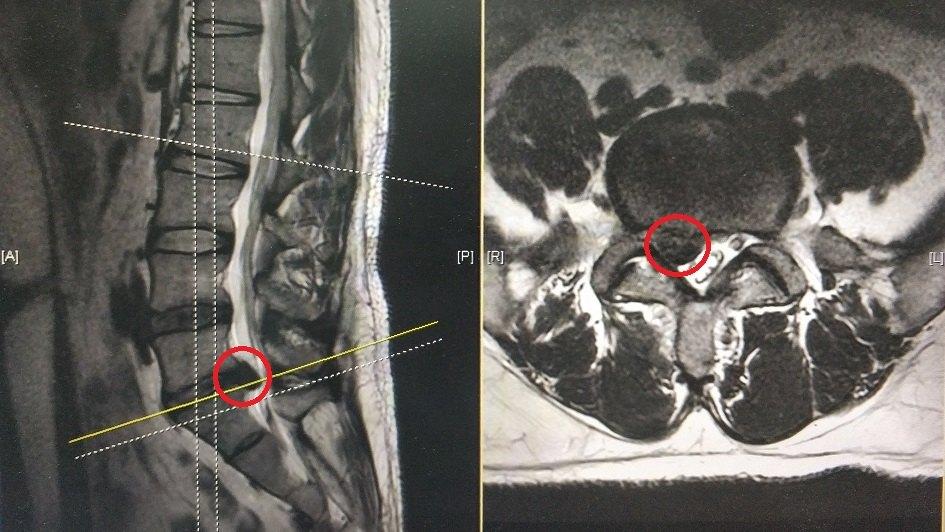

腰椎mri示:l5-s1椎间盘脱出并下游离,神经受压迫严重(下图中红色圈

图片尺寸945x532